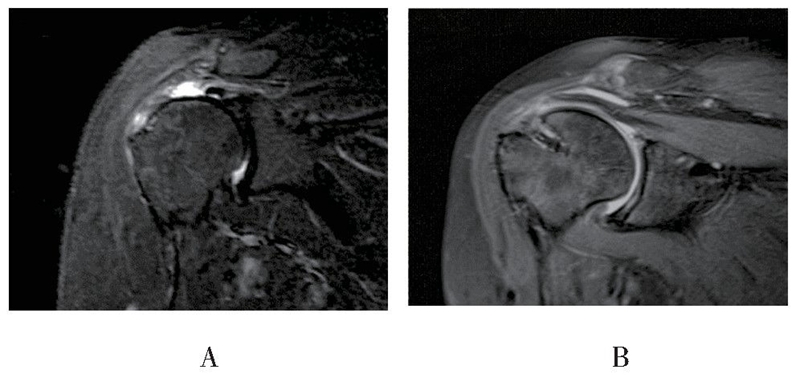

MRI随访见18例患者重建组织结构完整,愈合率达85.7%(18/21),3例出现明显结构失败,但失败患者功能恢复良好,未诉明显不适,因此未行翻修手术(见图5、图6)。

图5 患者女,67岁,末次随访时斜冠状位MRI显示右肩术后重建结构连续性完整A:术前磁共振影像,B:术后磁共振影像

图6 患者男,56岁,术后6个月随访时斜冠状位MRI显示右肩术后重建结构失败A:术前磁共振影像,B:术后磁共振影像